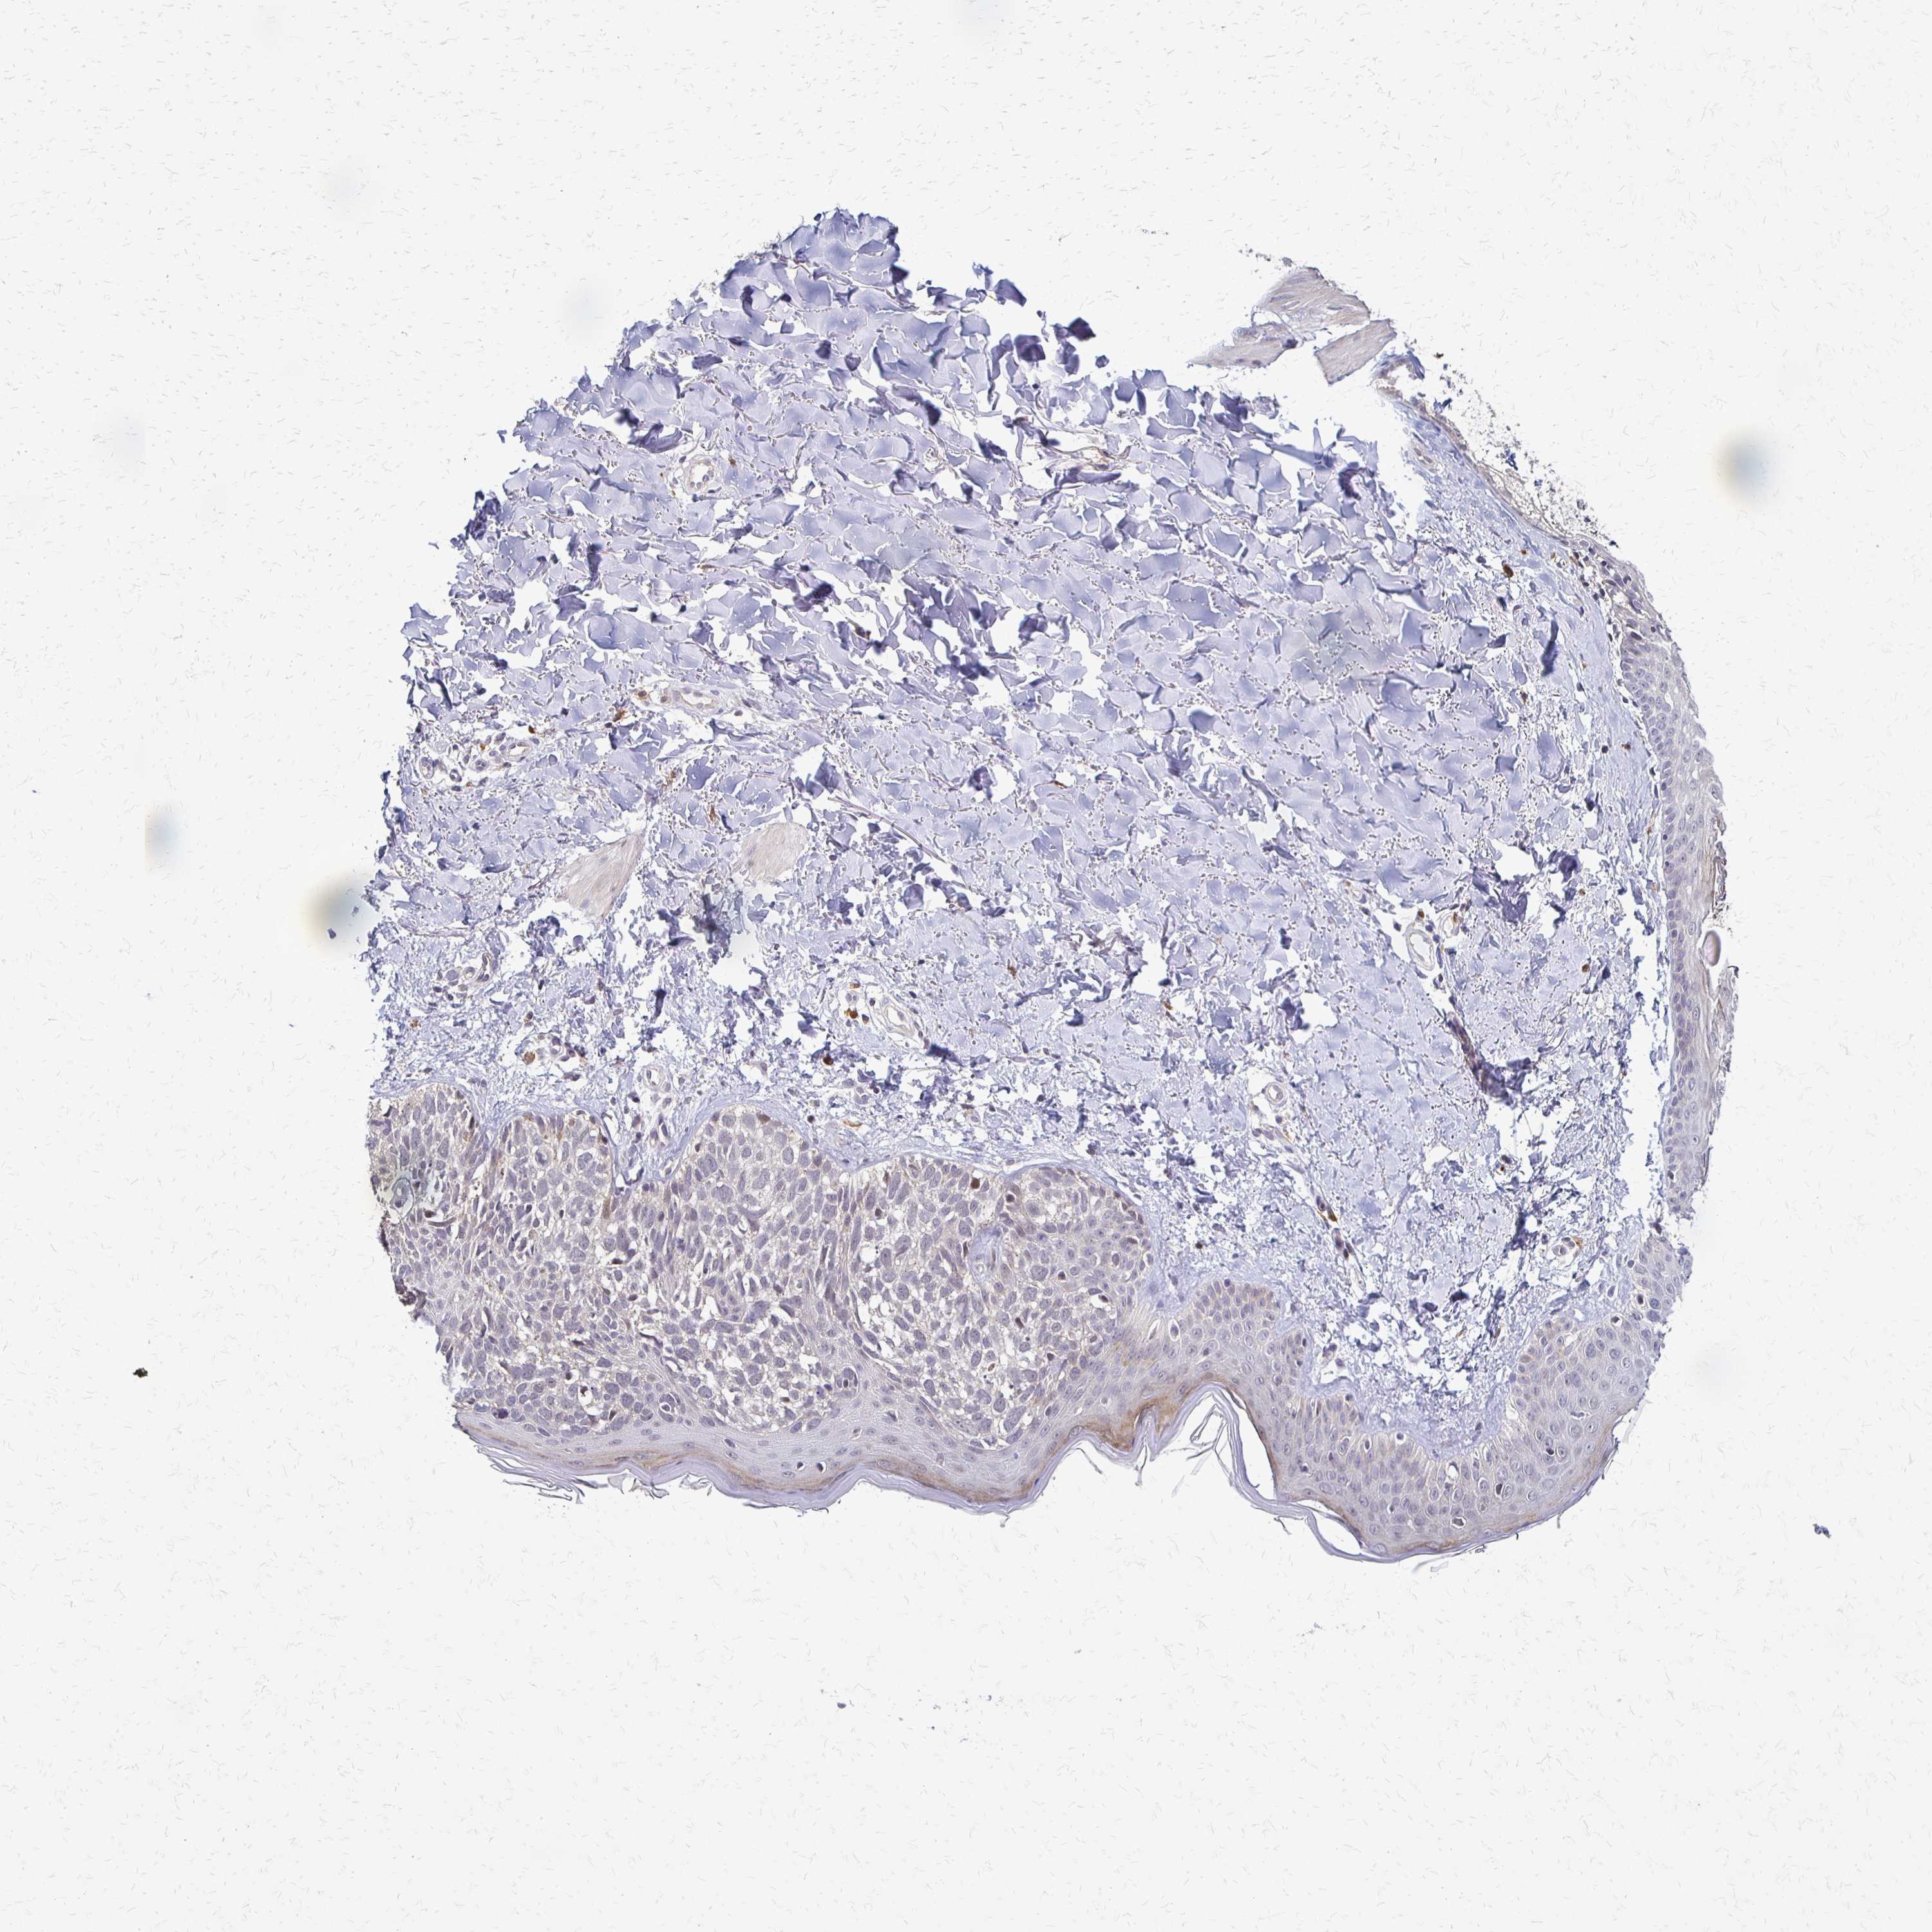

CANCER SKIN CANCER Show tissue menu

Basal cell and squamous cell cancer

SKIN CANCER - Protein expressioni

A mouse-over function shows sample information and annotation data. Click on an image to view it in a full screen mode. Samples can be filtered based on level of antibody staining by selecting one or several of the following categories: high, medium, low and not detected. The assay and annotation is described here.

Each image is clickable and will lead to virtual microscopy that enables deeper exploration of all samples and also displays staining intensity scores, fraction scores and subcellular localization as well as patient and tissue information for each sample.

Antibody HPA058234

Basal cell carcinoma

BCC, low aggressive